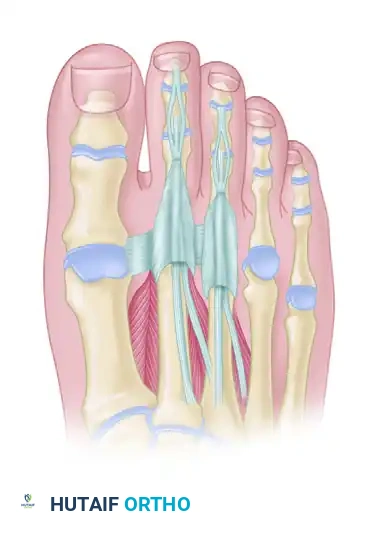

SURGICAL ANATOMY

Understanding the osseous and tendinous architecture of the forefoot is essential for precise surgical execution. The following diagrams illustrate the critical relationships between the phalanges, the MTP joints, and the extensor/flexor mechanisms.

Anatomical overview of the lesser toe osseous structures, highlighting the proximal, middle, and distal phalanges where osteotomies and arthroplasties are performed.

Detailed view of the MTP and IP joint articulations. Note the congruency of the joints which is disrupted in chronic claw and hammer toe deformities.

The tendinous anatomy of the lesser toes, demonstrating the central slip of the extensor digitorum longus and the intricate balance of the lumbricals and interossei.